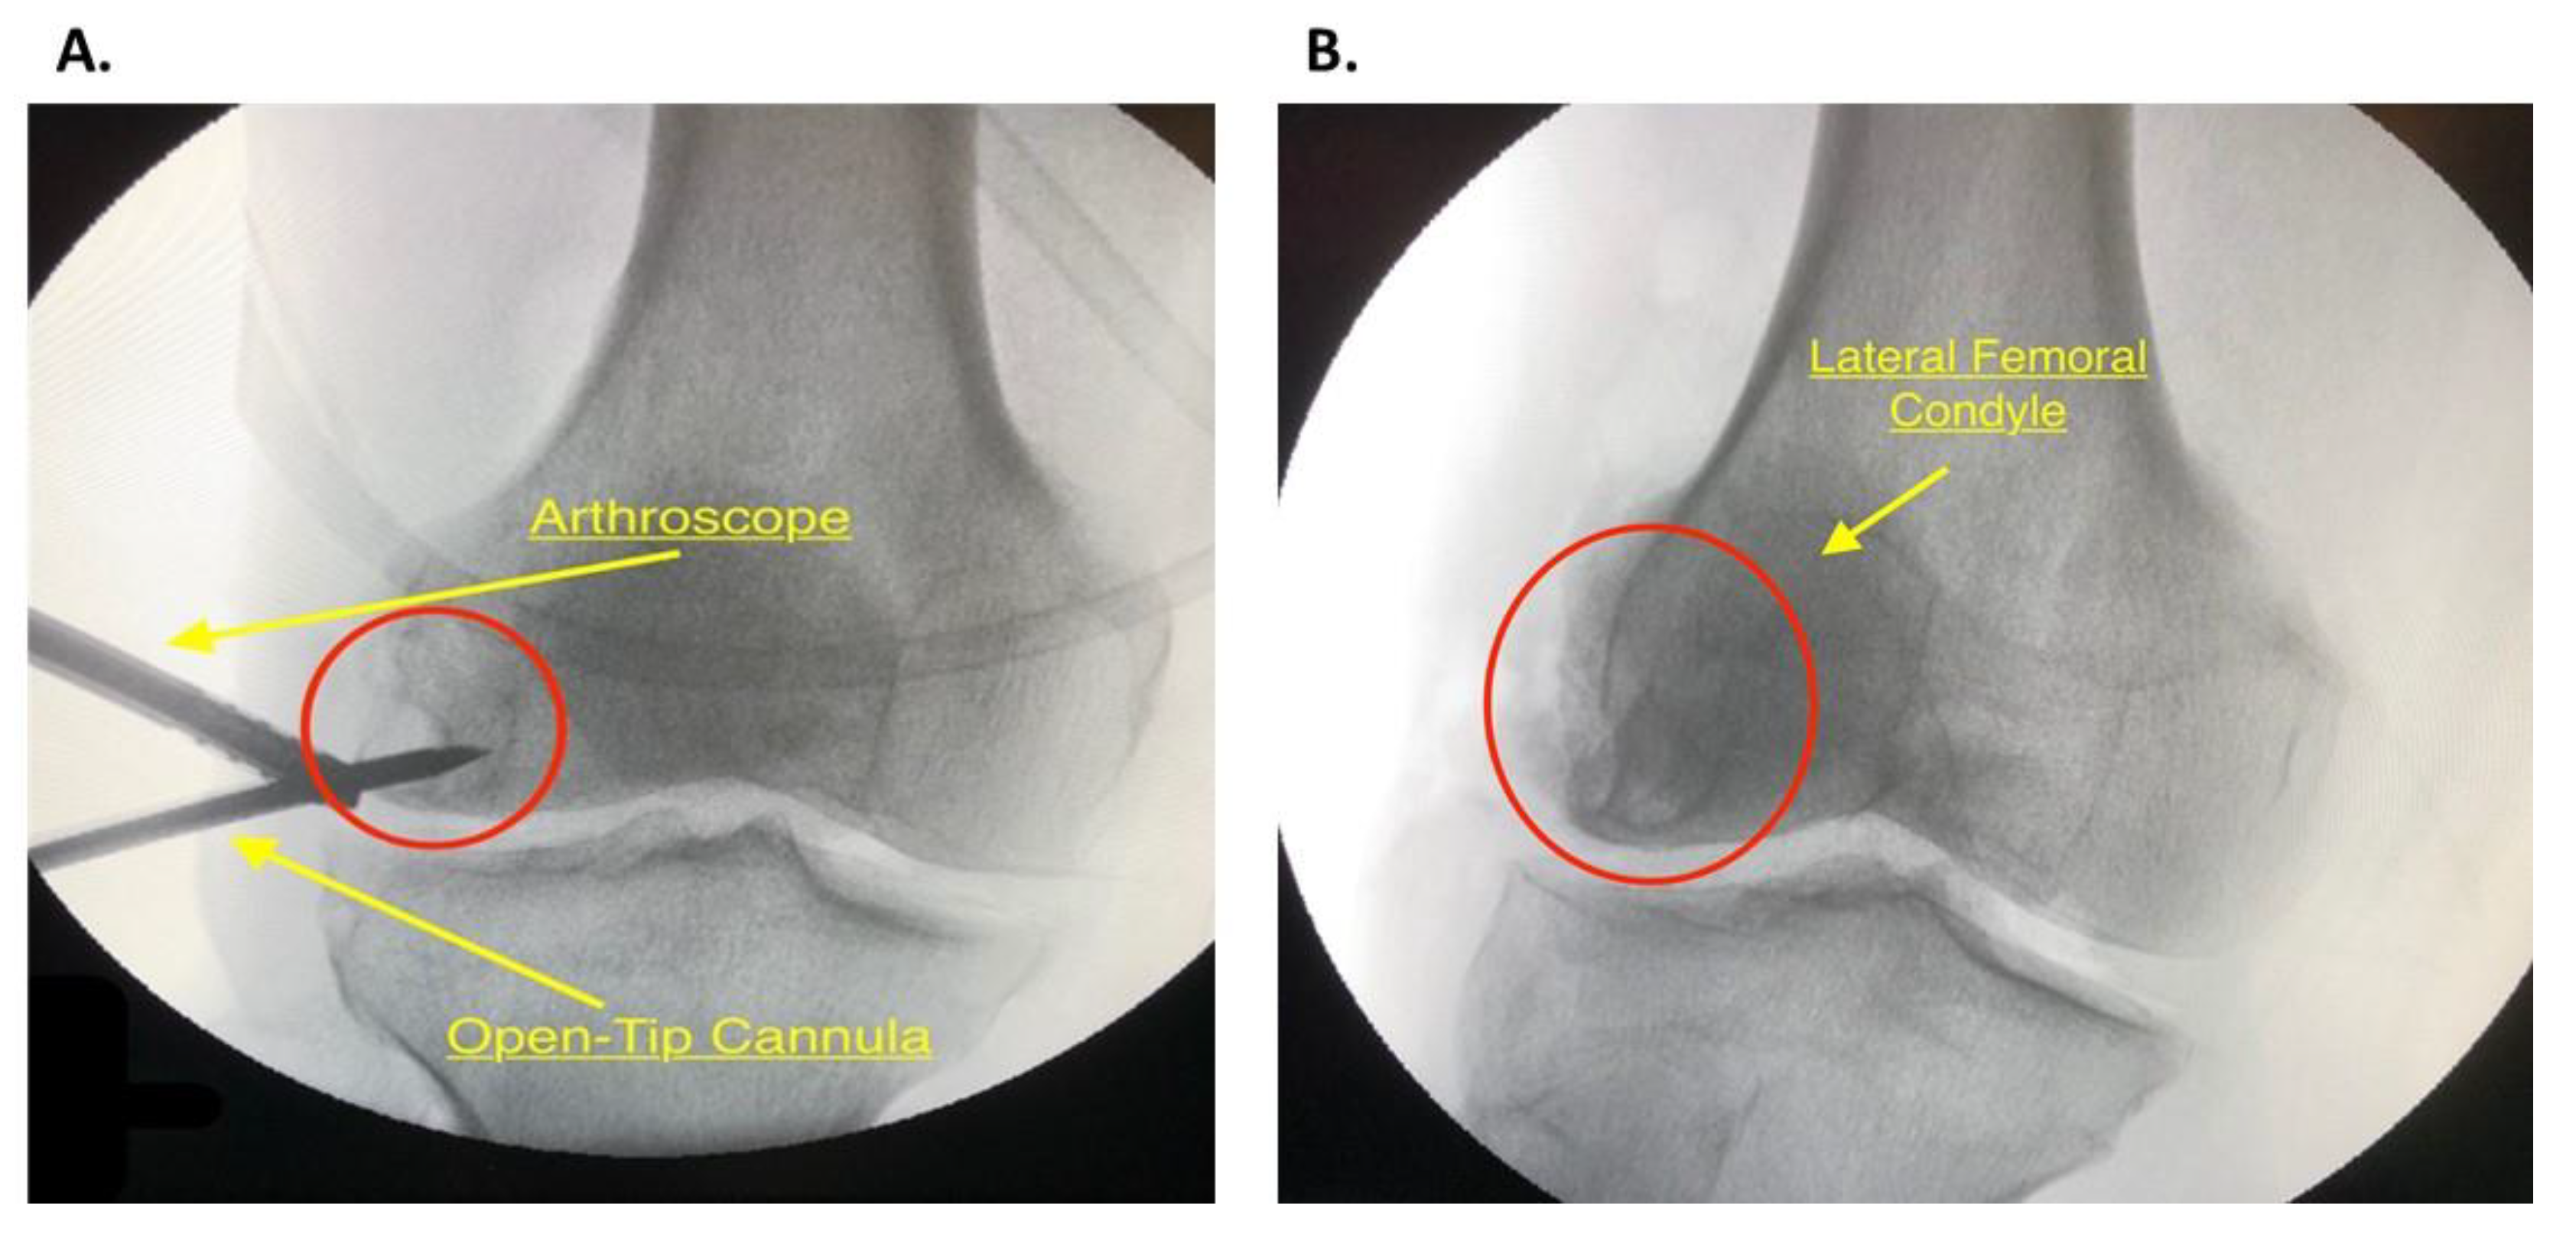

2.4. Diagnostic Arthroscopy